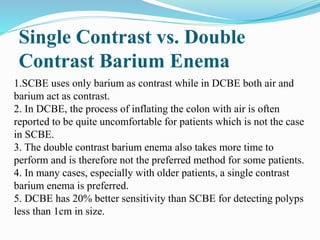

This document discusses colorectal polyps. It defines polyps and describes their types, including neoplastic and non-neoplastic polyps. It discusses adenomatous polyps in depth, noting their malignant potential increases with size over 1cm and villous architecture. Radiological diagnostic methods for polyps including single and double contrast barium enema and CT colonography are explained. The document provides an overview of polyp pathogenesis and genetic syndromes like FAP that increase cancer risk.